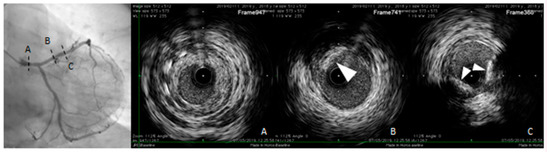

Non-contrast electrocardiographic (ECG)-gated multidetector CT provides a direct quantitative assessment of coronary artery calcium (CAC) [44]. (Figure 1). The standard method for CAC quantification is the Agatston score which measures the density of calcification in each coronary segment, multiplied by the area and summed for all arteries [45]. CAC score correlates with the total coronary plaque burden and is an independent predictor for CV events irrespective of ages [46,47,48,49,50,51,52]. Extensive calcification is associated with higher risk of CAD, because the presence of more plaques increases the chance that one may rupture. Current guidelines recommend CAC score assessment in individuals at low- to intermediate-risk in whom treatment decision may be improved by CV risk stratification [53,54,55,56]. In individuals without known atherosclerotic disease, a CAC score of zero is associated with a high negative predictive value in excluding significant CAD [57]. However, although only 5% of individuals with zero CAC have significant stenosis, low CAC scores do not exclude obstructive CAD [57,58,59]. Instead, a CAC score >100 is associated with a risk of events similar to patients with previous CAD [60,61].

Figure 1.

Calcium scoring (CAC) performed on a non-contrast ECG-gated CT scan of a patient with coronary arteries calcifications using commercial software Vitrea 6.0. The software automatically highlights all the structures attenuating at least 130 Hounsfield units (pink). Regions of interest (ROI) were manually placed around the coronary arteries calcifications using different colors for each coronary segment. The partial and overall Agatston score and volume of the calcifications included in the regions of interest are summarized in the box on the bottom of the images. (A) Calcifications in the left main, anterior descending and 1st diagonal branch. (B) Calcification in the proximal segment of the right coronary artery.